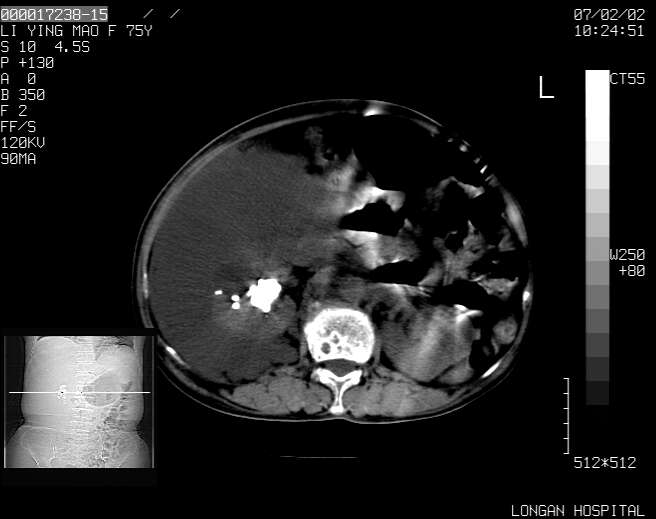

以下是引用dyqct在2007-2-10 8:53:00的发言:[br]考虑:1、肝脏多发囊肿[br] 2、左肾囊肿,右肾多发结石并积水。[br] 3、右胸少量积液。[br] 4、右肾周包裹性积液或淋巴管瘤(有见缝就钻的征象、薄隔、小结节状钙化)?[br] 5、腰椎动脉瘤样骨囊肿?[br] [br] [br]